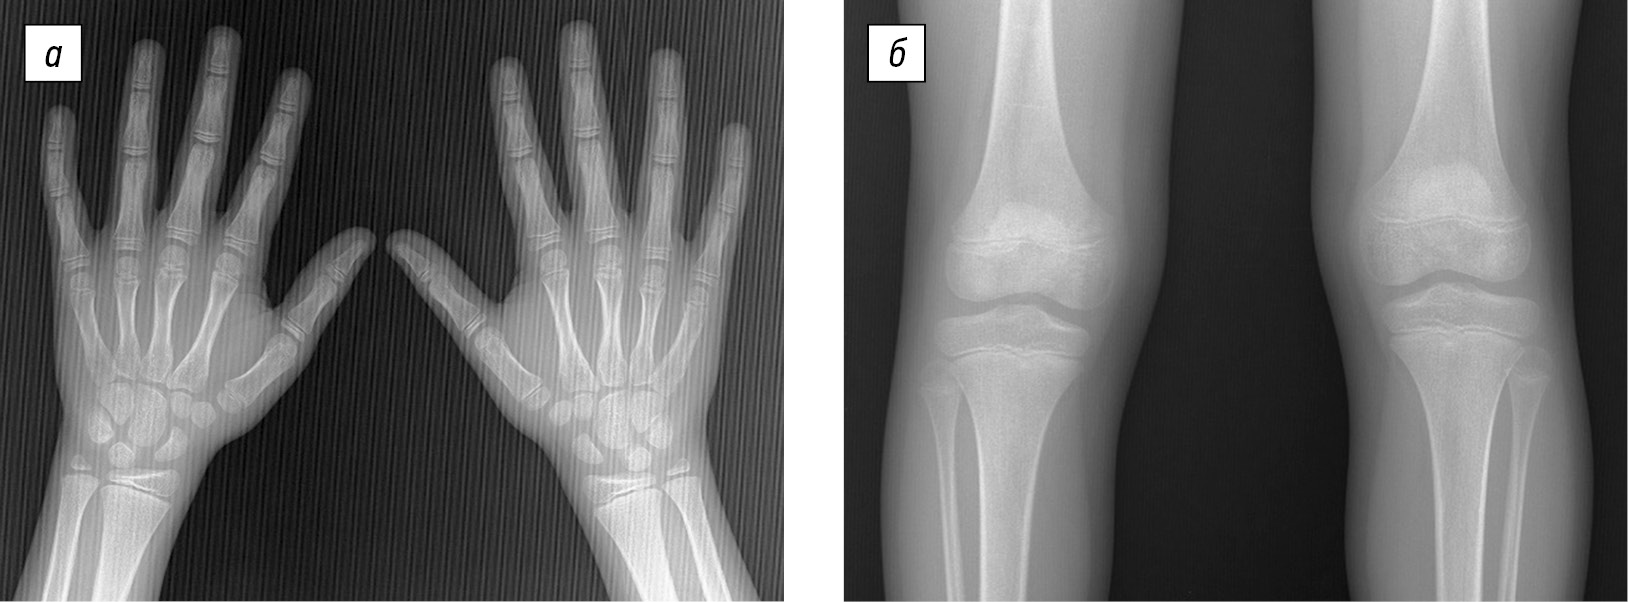

Рентгенограммы кистей и коленных суставов без значимых изменений (рис. 3).

Рис. 3. Рентгенограммы кистей и коленных суставов в прямой проекции